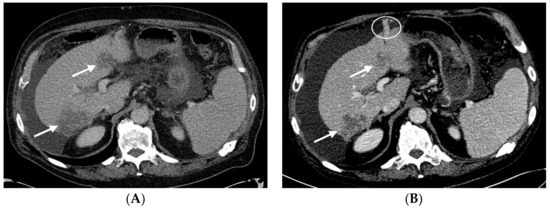

2.1. Patient #1

2.2. Patient #2